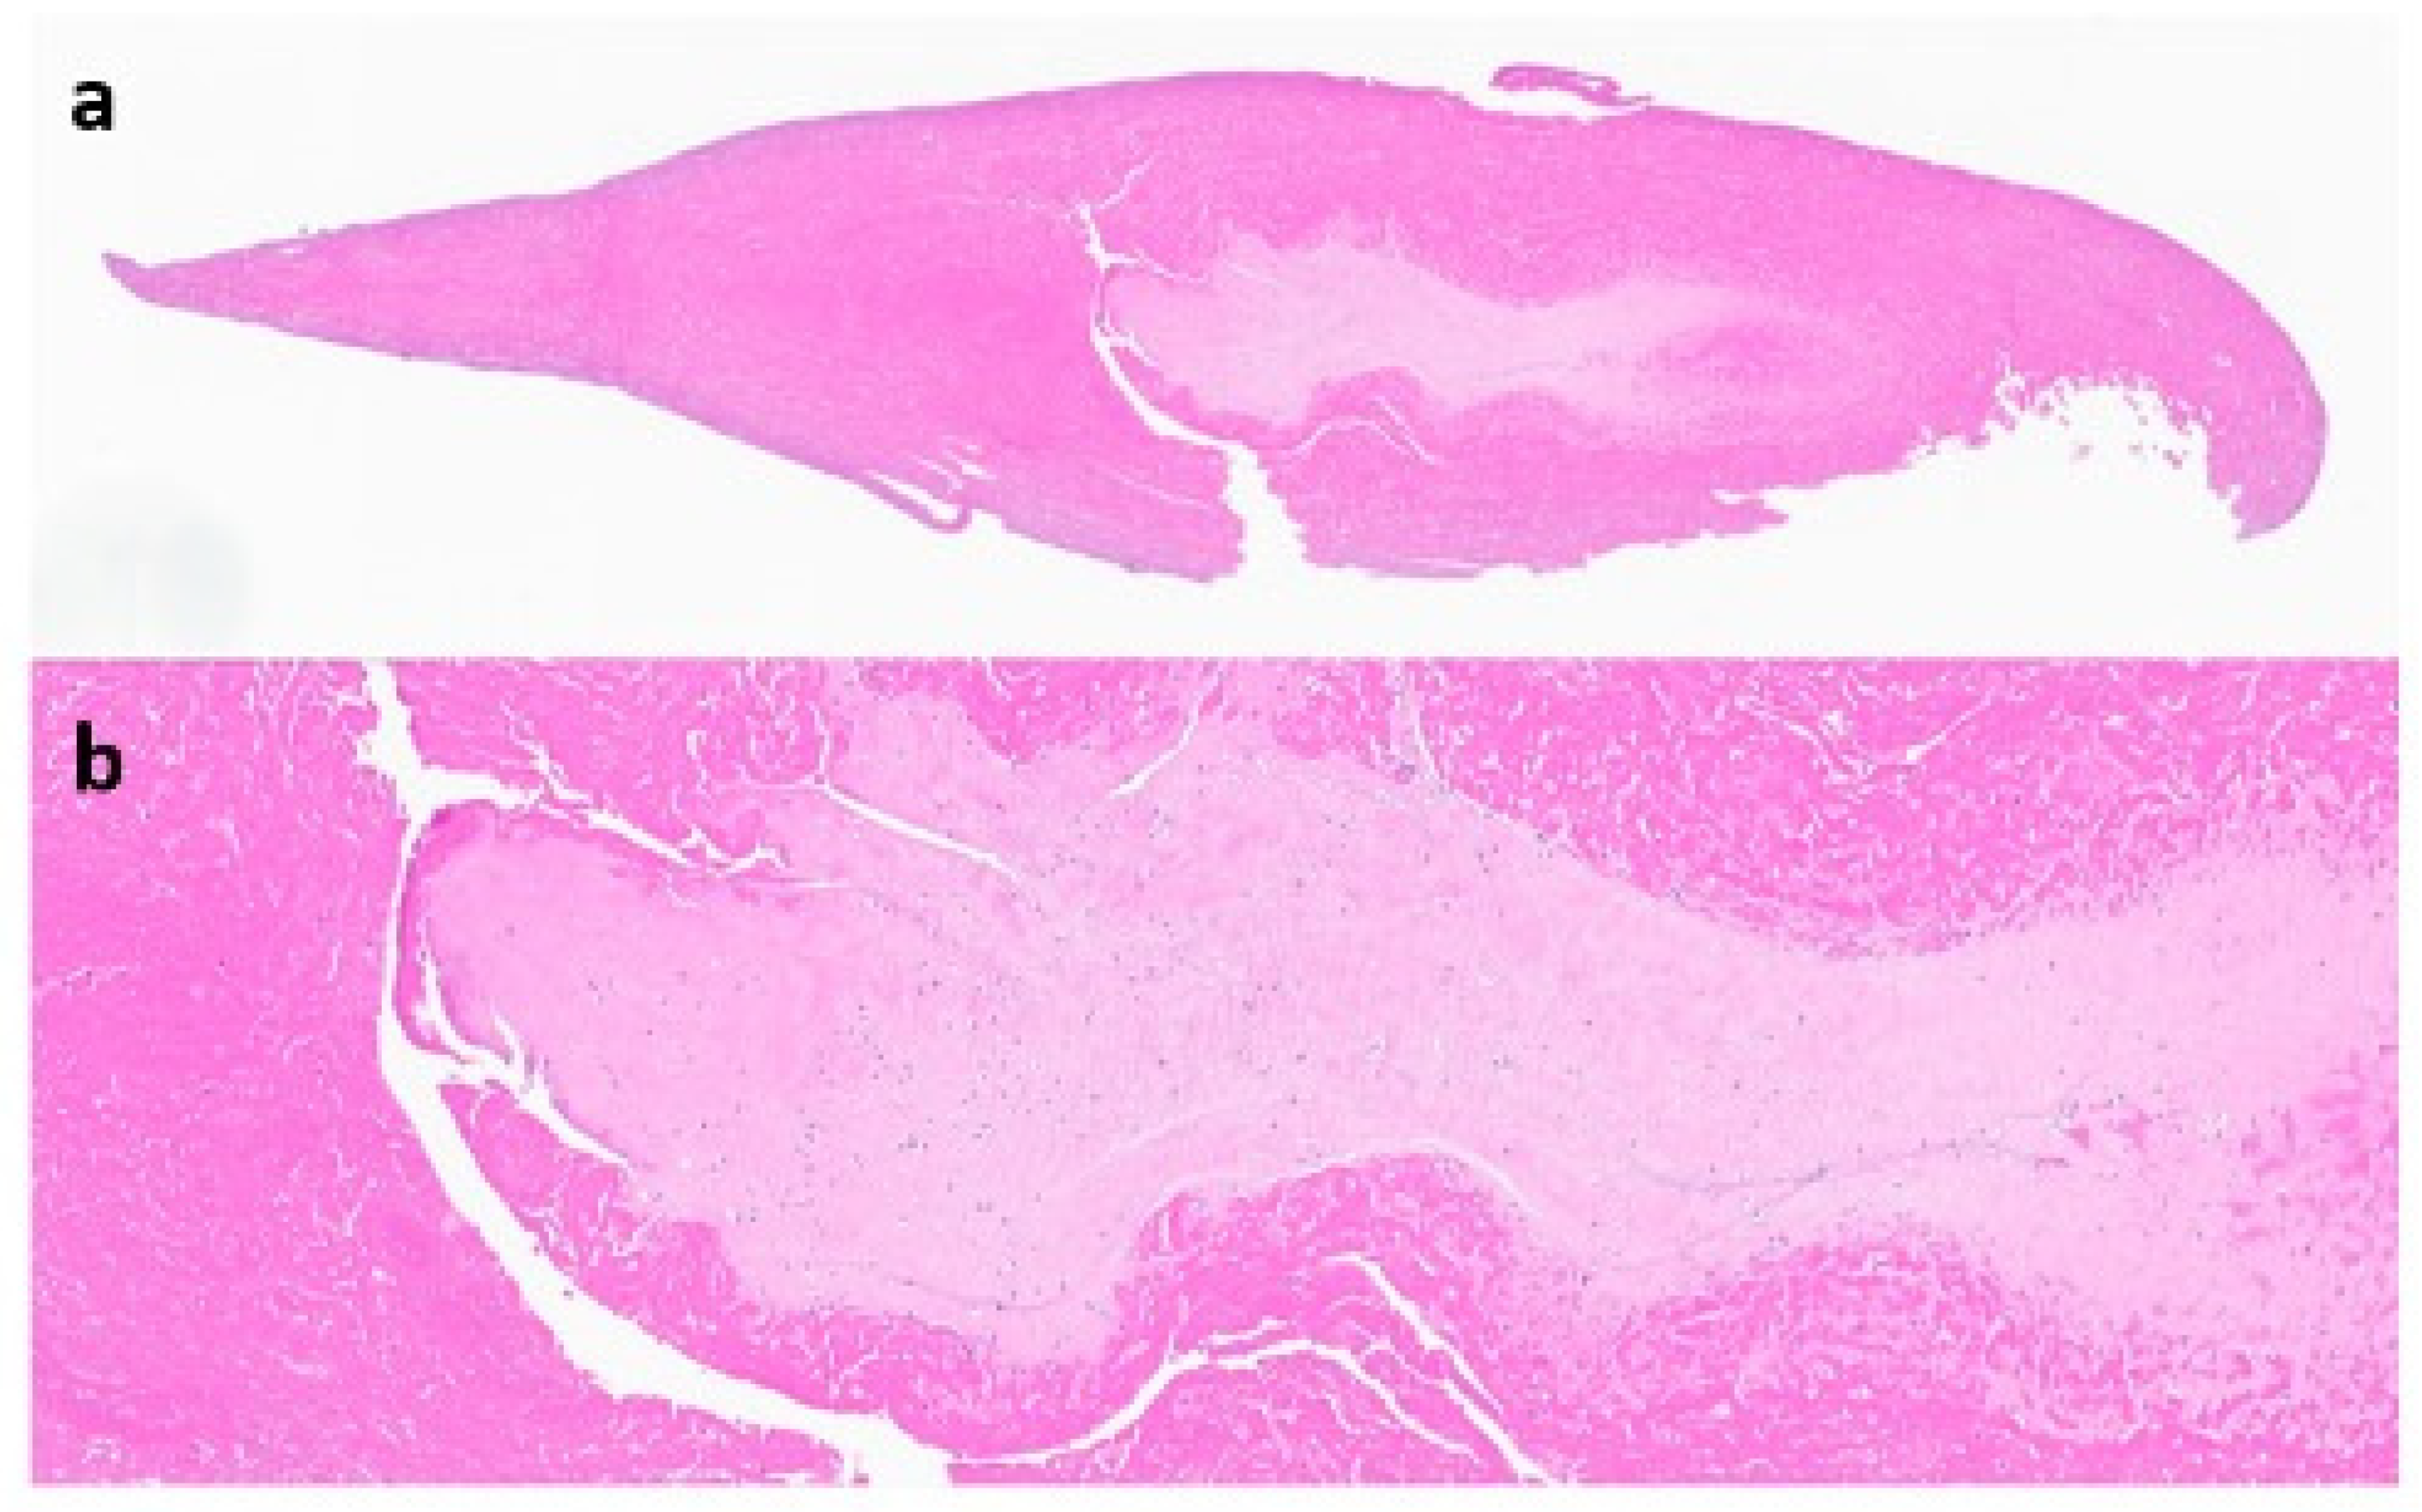

This case report refers to a 62-year-old woman who received a right TKA for primary osteoarthritis (OA) in August 2018 at the age of 58 years at an outside hospital. Informed consent was obtained from the patient with an explanation that the data concerning her case would be submitted for publication. The patient’s x-ray and MRI images showed no evidence of SC prior to her TKA surgery, as seen in Figure 1. The synovial tissue samples of the knee joint obtained during her index right TKA surgery also showed no evidence of SC, but showed synovial hyperplasia with lymphocytic infiltration, as this can occur in the context of degenerative joint disease or in association with RA.

Figure 1. X-ray from 11 June 2018 ((a)—lateral view, (b)—anterior–posterior view) and MRI from 13 March 2017 ((c)—axial view, (d)—sagittal view); right knee shows knee osteoarthritis with no sign of synovial chondromatosis prior to TKA in August 2018.